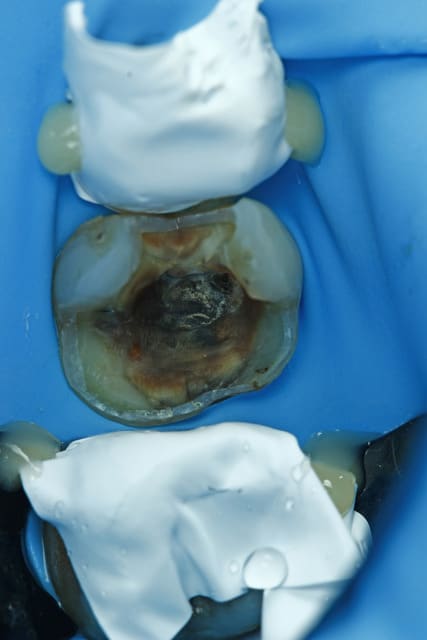

nic Tone en action ;)

--

Dr Cingulum

-----Ancien interné----

----Attaché à l'apex----

http://www.clinic-all.fr/ formation par passion